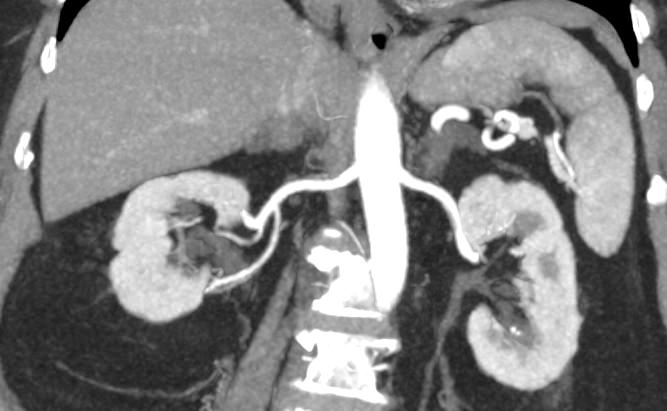

Мультиспиральная КТ сосудов почек (КТ-ангиография) с внутривенным болюсным контрастированием проводится для диагностики патологии почечных артерий. С помощью КТ-ангиографии можно выявить врожденные аномалии развития сосудов почек, диагностировать стенозы (уменьшение просвета) почечных артерий за счет развития атеросклеротических бляшек.

КТ сосудов почек применяется для выявления признаков вторичной артериальной гипертензии, при планировании оперативных вмешательств и для оценки успешности проведенной операции на сосудах. КТ ангиография почечных артерий позволяет оценить их анатомию, выявить добавочные и аберрантные почечные сосуды, определить типично ли они распространяются в ворота почки или заходят в паренхиму через корковый слой.

Чувствительные детекторы улавливают рентгеновские лучи после их прохождения сквозь тело человека. На основании этих данных получаются изображения сосудистой системы почек в мельчайших подробностях. Кроме того, с помощью цифровой обработки данных томограф реконструирует трехмерные модели кровеносных сосудов на уровне исследуемой области. 3D-реконструкции помогают увидеть пространственное соотношение анатомических структур и значительно повышают качество диагностики.

В наших медицинских центрах КТ-ангиография почечных артерий выполняется на новейших мультиспиральных компьютерных томографах экспертного класса TOSHIBA AQUILION. Аппараты сканируют область почек, производя одномоментно множество послойных срезов исследуемой зоны, благодаря этому создаются изображения кровеносной системы высокого качества. Это позволяет проводить точную и достоверную диагностику патологии почечных артерий. При этом за счет скоростного мультисрезового сканирования пациент получает минимальную дозу рентгеновского облучения.